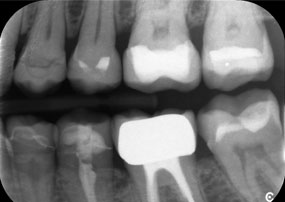

Provocarea consta în îndepărtarea a douăsprezece coroane fixate cu aliaj metalic, fără a deteriora dinții de susținere. Piesa de mână a fost utilizată pentru secționarea foarte precisă a straturilor ceramice și divizarea structurii metalice cu ajutorul unei freze din carbură, permițând astfel îndepărtarea coroanei cu un grad minim de traumatizare. În doar 30 de minute, vechile restaurări au fost îndepărtate, permițând pregătirea noii proteze, cu contur complet din zirconiu în regiunea posterioară și coroane fațetate anterior. Rezultatul a fost o restaurare completă, care a asigurat atât succesul funcțional, cât și cel estetic (vezi Fig. 1).

Un al doilea caz, care evidențiază capabilitățile clinice ale piesei Synea Power Edition, a implicat înlocuirea unei coroane din zirconiu deteriorate, la o pacientă în vârstă de 63 de ani. Pacienta prezenta o fațetă ciobită pe o coroană din zirconiu veche de 20 de ani, pe primul molar (#6). În ciuda localizării posterioare, pacienta considera defectul deranjant și a solicitat o nouă restaurare.

Piesa Power Edition a permis secționarea precisă, cuplul crescut și răcirea îmbunătățită contribuind la îndepărtarea controlată a coroanei, fără pierderi semnificative de material. Sistemul de prindere și cuplul îmbunătățit s-au dovedit esențiale în acest proces.